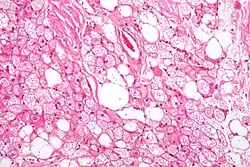

Hibernoma (intermediate magnification).

The tumors histologically resemble brown fat. There are four histologic types recognized, but one is the most frequently seen (typical). There is a background of rich vascularity.

- Lobular type: Variable degrees of differentiation of uniform, round to oval cells with granular eosinophilic cells with prominent borders, alternating with coarsely multivacuolated fat cells (pale cells). There are usually small centrally placed nuclei without pleomorphism. The cells have large cytoplasmic lipid droplets interspersed throughout.[4][5]